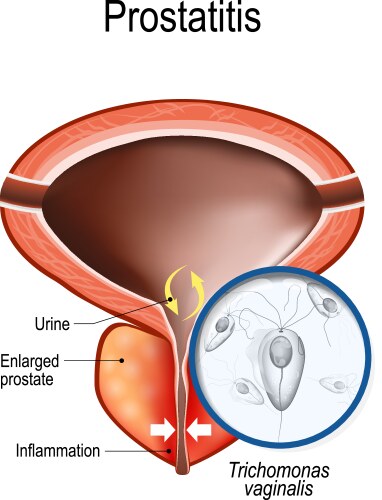

- Prostate

- Bladder

- Disease

- Disorder

- Infection

- Urine